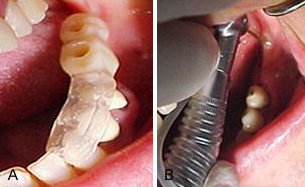

Figuras n° 13 A e B.

A) Vista oclusal do guia cirúrgico em posição na cavidade bucal, mostrando o hexágono do parafuso do monta implante que será usado para transferir a posição de fixação para o modelo de trabalho. Nota-se que devido à espessura e altura do monta implante e sua ligeira inclinação para vestibular, o orifício para a orientação do posicionamento da broca inicial, no instante desta transferência foi aumentado, possibilitando a adaptação correta do guia cirúrgico. B) vista vestibular mostrando correta adaptação do guia cirúrgico.

Figura n°15. Prova estética do pilar.

Figuras n°15, A e B. A) Preparo do pilar utilizando a broca diamantada em alta rotação. B) Vista do pilar em posição no modelo de trabalho, sobre este, utilizando R.AAQ. de mesma cor da faceta previamente preparada, a partir do dente de estoque, será confeccionada a coroa estética provisória. Esta deverá ter assentamento perfeito sobre o bordo preparado no pilar e produzindo o perfil emergente esperado e com correto polimento.

Figura n°16, A e B. A) Radiografia digitalizada (Digora) mostrando a correta adaptação entre a superfície de assentamento do implante e o hexágono externo do pilar. B), coroa estética em posição na cavidade bucal e cimentada sobre o pilar.

Figura n°17, A. Aspectos da coroa 2 semanas após a cirurgia e cimentação da coroa estética.